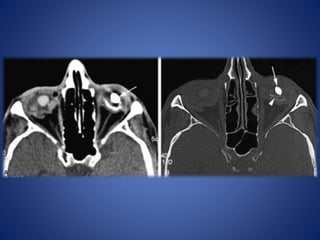

Metallic foreign body inside the globe

Non-metallic foreign body

• #5 Ocular rupture. Axial CT scan shows deformity of the left eye with uveoscleral infolding due to ocular hypotony related to a rupture.

• #6 Ocular trauma and choroidal hematoma. Axial CT scan shows a hyperdense left choroidal hematoma. This can be confused with a choroidal melanoma.